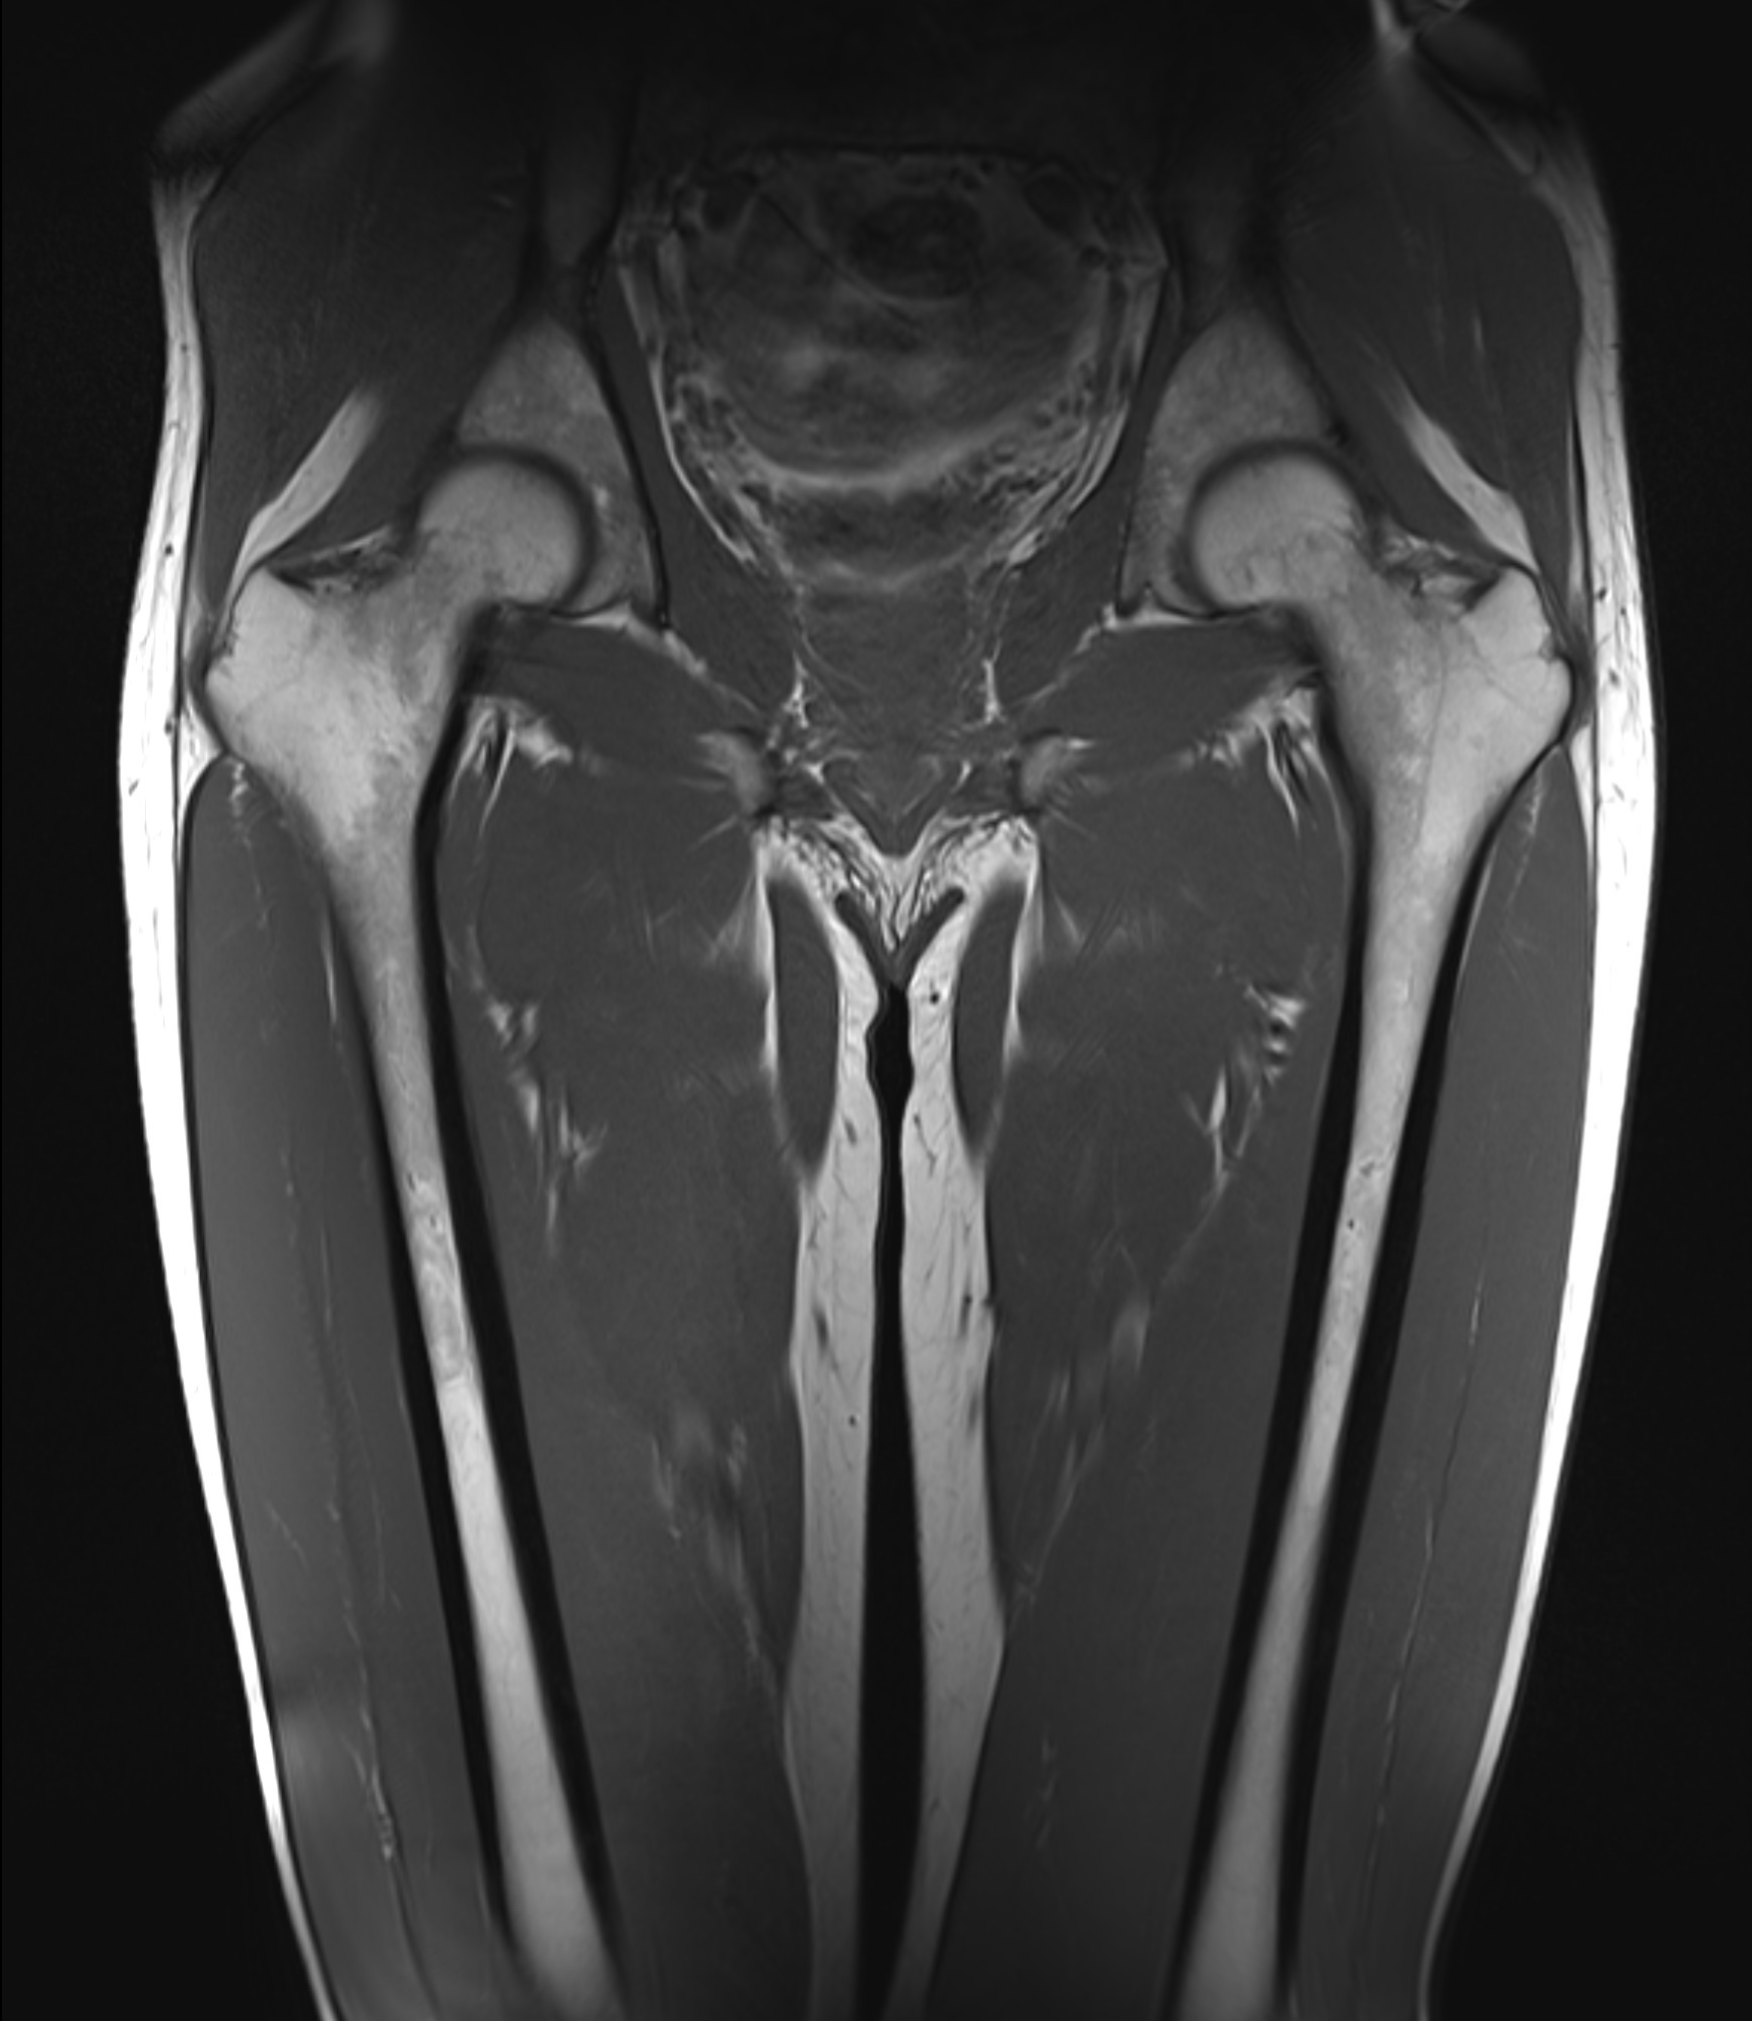

MR Lårben – Magnetkameraundersökning vid smärta, fraktur eller misstänkt skelettsjukdom

Lårbenet (femur) är kroppens längsta och starkaste ben – en central struktur för gång, belastning och rörelse. Trots sin styrka kan lårbenet drabbas av frakturer, stressreaktioner, infektioner, tumörer eller inflammationer som påverkar både funktion och livskvalitet. Med en magnetkameraundersökning (MR) av lårbenet får du en mycket detaljerad bild av skelett, benmärg, muskler, senor och omgivande mjukdelar. Undersökningen är helt utan strålning, smärtfri och särskilt användbar när andra bilddiagnostiska metoder inte har gett tillräcklig information.

MR lårben är ett värdefullt diagnostiskt verktyg vid smärta som inte förklaras av röntgen, vid misstänkta stressfrakturer, efter trauma eller vid symptom som tyder på underliggande skelettsjukdom. Det används ofta för att utesluta allvarliga tillstånd eller kartlägga omfattningen av en skada.

MR är särskilt värdefullt om andra undersökningar (t.ex. slätröntgen eller ultraljud) inte visar några avvikelser, men symptomen kvarstår. Det används även för att följa upp läkning av skador eller infektioner i benvävnad.

En MR-undersökning av lårbenet är ett träffsäkert sätt att diagnostisera dolda skador eller sjukdomar i skelett och mjukdelar. Undersökningen är helt smärtfri, tar cirka 20–30 minuter och kräver ingen remiss. Bilderna granskas av specialistläkare och ett skriftligt utlåtande levereras inom några dagar.